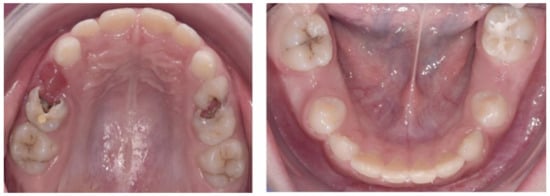

2.3.2. Second Phase of Treatment—2017—Bite-Blocks and Transpalatal Arch

3. Results